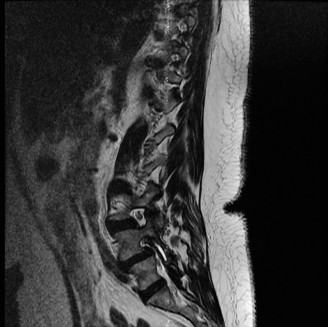

clinical practice to assess cervical spine disease. A positive Hoffman’s sign reflects the presence of an upper, motor neuron lesion from spinal cord compression. An inverted radial reflex can also be a sign of upper, motor neuron compression and dysfunction. It is elicited by tapping the brachioradialis tendon, which produces reflexive flexion in the thumb and index finger. A pectoralis reflex is elicited by tapping the tendon in the shoulder/chest region. An MRI is obtained (Fig. 1–27). Plain radiographs reveal a relatively fixed alignment on dynamic views with no evidence of gross instability. Which of the following is the most appropriate treatment plan for this patient? 1. Physical therapy

2. Cervical laminoplasty C3–7

3. Laminectomy and fusion C3–7

4. Anterior corpectomies of C5–6

Figure 1–27

Discussion

The correct answer is (D). Cervical laminoplasty or laminectomy is not recommended in the presence of greater than 13 degrees of kyphosis. In this setting, anterior decompression is preferred. Corpectomy is a reasonable option. When performing three consecutive corpectomies (in this case only two; C5 and 6), posterior instrumentation and fusion are recommended as there is a high risk of anterior strut dislodgement with stand-alone anterior constructs. Continued physical therapy (i.e., nonoperative treatment) is not recommended as CSM has a poor natural history. Objectives: Did you learn...? The differential diagnosis of a patient presenting with symptoms and signs of CSM?